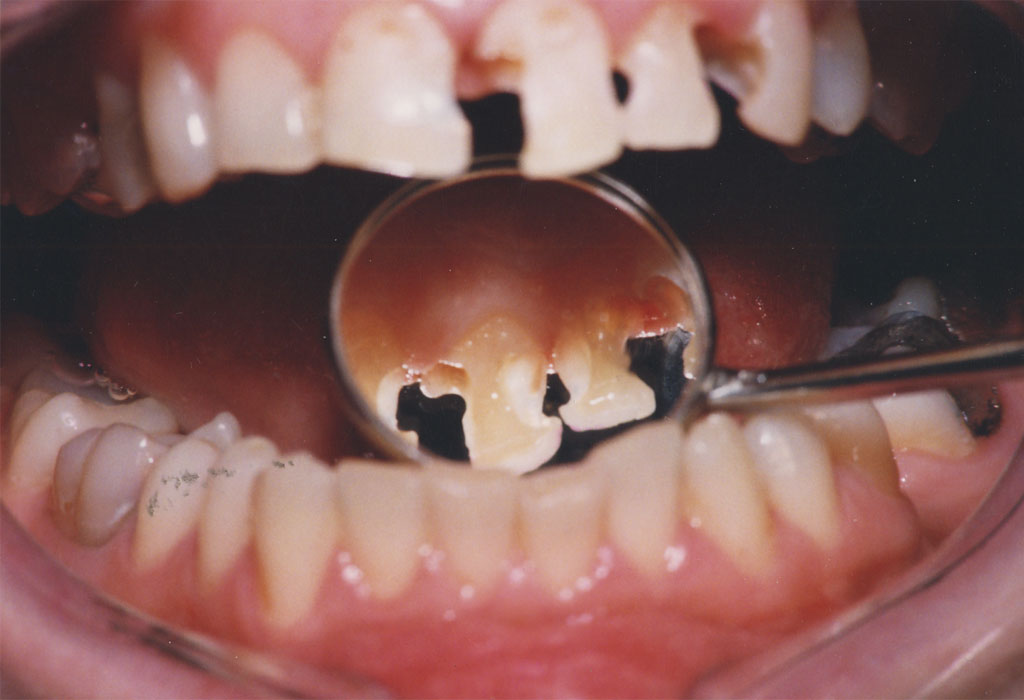

Lečenje zuba podrazumeva postupak uklanjanja nerva iz samog zuba. Naš tim se edukavao iz oblasti savremenih principa endodontske terapije i mašinske endodoncije kako bi svojim pacijetima ponudili najkvalitetnije usluge iz navedene oblasti.

Znanje i aparatura koju posedujemo omugućuje nam da obradu kanala korena zuba sprovodimo uoptrebom mašinskih rotirajućih instrumenata (ProtaperNext), irigansa propisanih od strane evropske asocijacije endodonata i savremnih tehnika punjenja kanala korena. Na taj način zubi su besprekorno izlečeni i traju dug vremenski period.